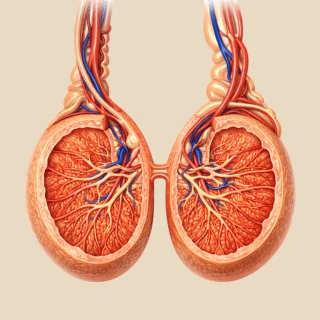

Nefrectomía

Resección parcial o total del riñón, indicada principalmente para el tratamiento del cáncer renal; por lo tanto, es un procedimiento clave en la urología oncológica.